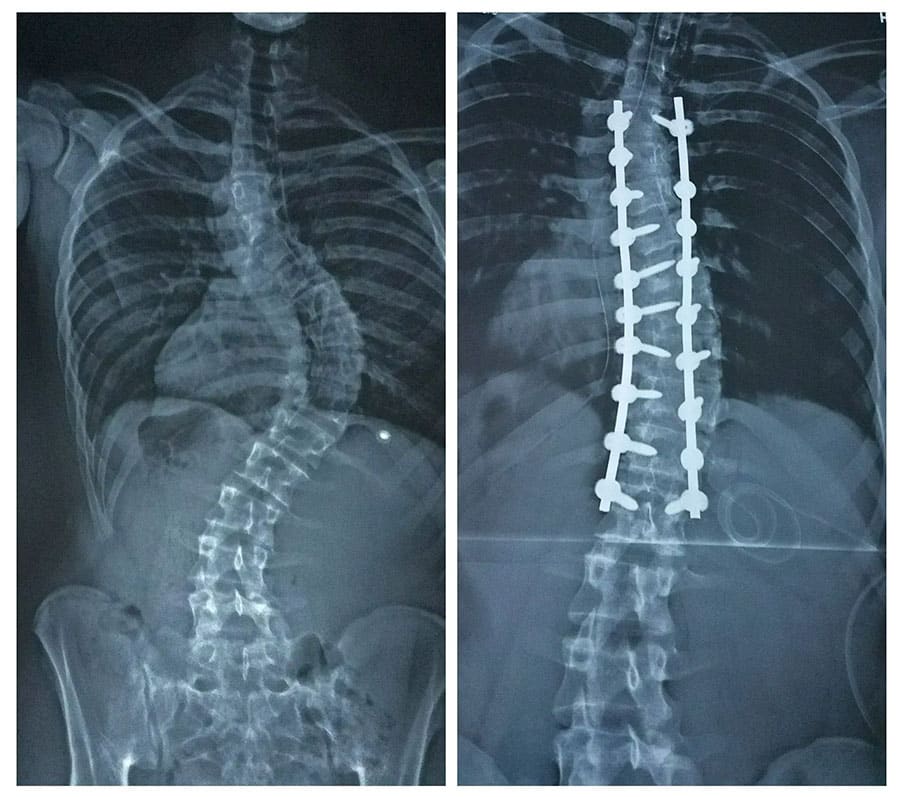

While there are many different spine surgeries used for those with scoliosis or kyphosis, by far the most common is spinal fusion.

Some scoliosis and kyphosis curves progress to needing surgical correction. This is a large surgery and can be challenging to recover from. If you follow the right protocol, enlist the right professionals to help with your recovery, and take care of yourself, you will have a good result.